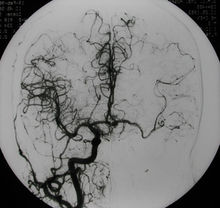

根据病史,临床表现及影像学检查尤其是DSA检查结果可以明确诊断。